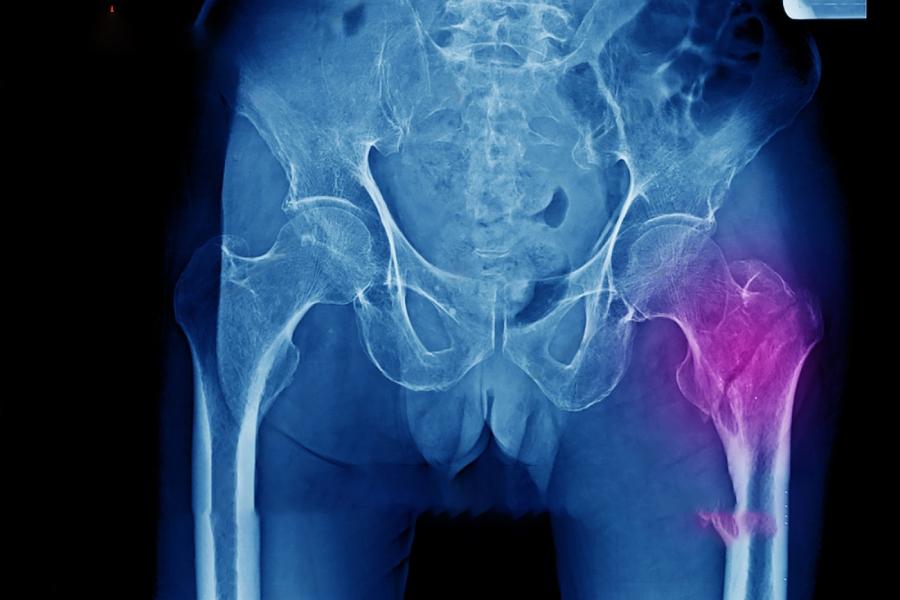

Femoroacetabular impingement (FAI): abnormal contact between the femur and pelvis

Hip dysplasia or congenital hip abnormalities